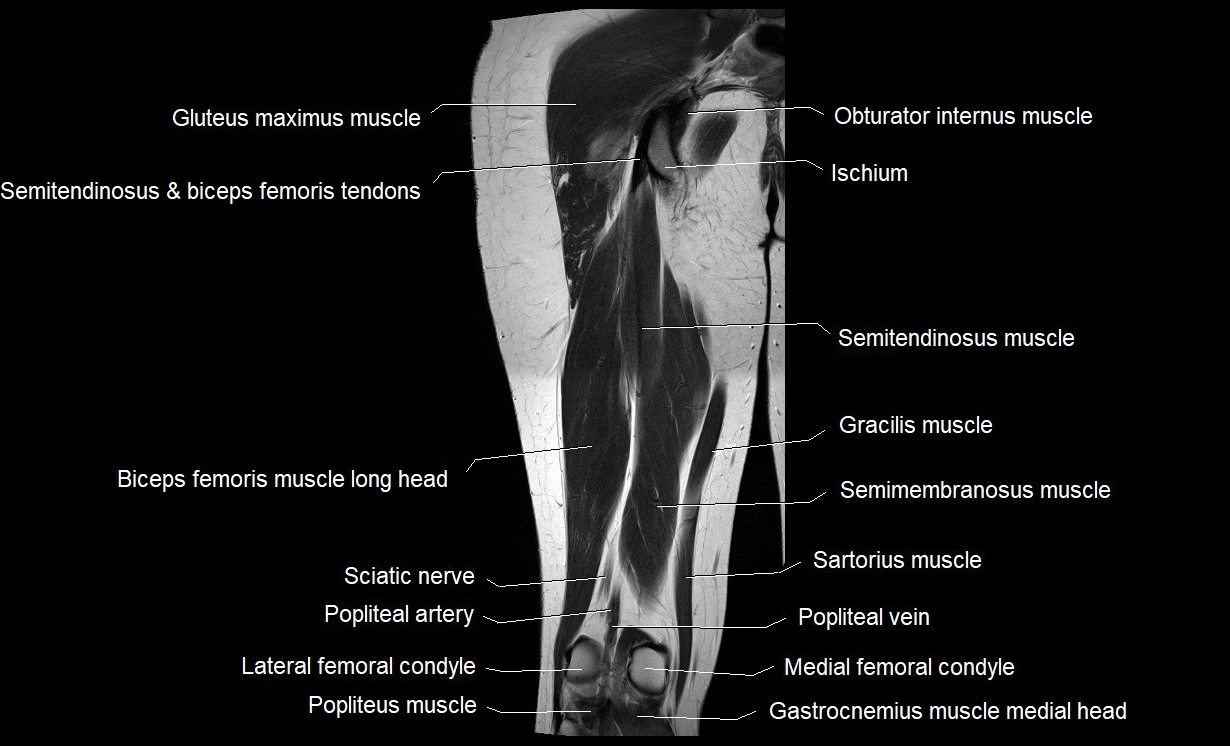

- Biceps femoris muscle (Long head)

- Gluteus maximus muscle

- Gracilis muscle

- Obturator internus muscle

- Popliteal artery

- Popliteal vein

- Popliteus muscle

- Sartorius muscle

- Semimembranosus muscle

- Semitendinosus muscle

- Tibial nerve